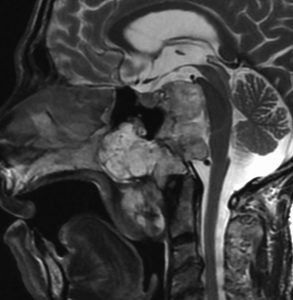

MRI T2強調画像(左)では等信号から高信号のまだらな境界が不明瞭な腫瘍が斜台から左海綿静脈洞内に浸潤しているのがみられます。T1強調ガドリニウム増強では,腫瘍がまだらに増強されています。トルコ鞍から鞍上部に伸び,視交差を侵し第3脳室底まで伸展しています。脊索腫が硬膜内に浸潤して神経組織と癒着することは珍しいことではありません。